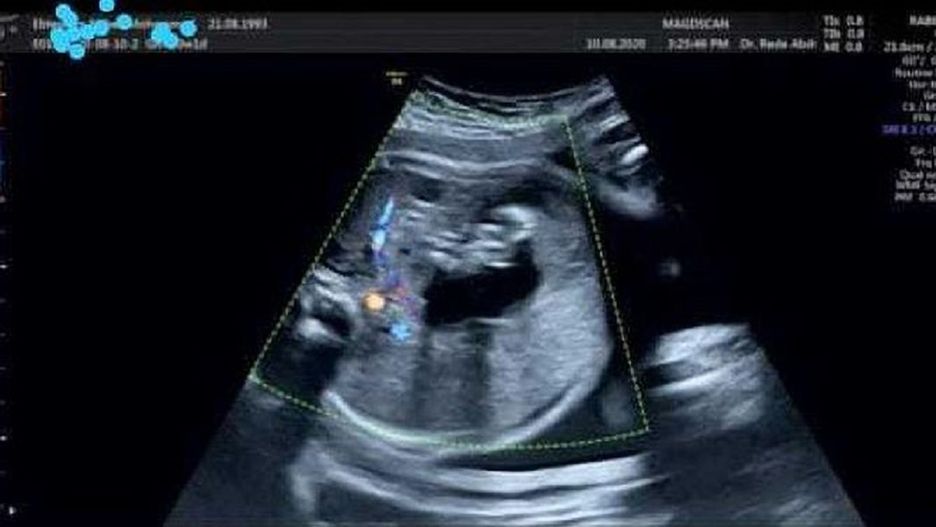

Lekarz prowadzący ciążę zauważył podczas badania kontrolnego ciało obce w brzuchu dziecka. Jednak chirurdzy doszli do wniosku, że nie zagraża on życiu i postanowili zoperować noworodka zaraz po porodzie. Ciąża trwała 9 miesięcy, a dziecko urodziło się zdrowe.

"W brzuchu dziecka w siódmym miesiącu ciąży zauważyłem ciało obce, ale wtedy nie pojęliśmy się operacji. Po raz pierwszy widziałem taką sytuację" - powiedział profesor położnictwa i ginekologii na Uniwersytecie Zagazig, dr Amr Abd El-Mohsen, który nadzorował poród.

Lekarze byli w szoku, gdy zobaczyli wyniki badań ukazujące płód w brzuchu noworodka. Był to pierwszy przypadek potworniaka w tej części Egiptu.

"Dziecko pozostawało pod obserwacją 24 godziny. Po wykonaniu tomografii komputerowej znaleźliśmy zarodek w jego brzuchu i wykonaliśmy operację usunięcia płodu – powiedział dr Mohamed Al-Akrasha. - Początkowo ciąża była bliźniacza, jednak jedna z embrionalnych torbieli weszła do jamy brzusznej drugiego dziecka".